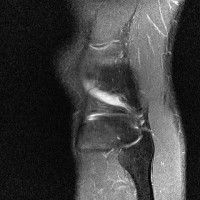

무릎 mri 간단히 봐주실 수 있으시나요 ㅠㅠ

안녕하세요 8년전 십자인대 수술하고 최근 무리한 운동에 무릎 불편감이 생겨서

mri 찍었습니다.

진단결과는 첫 찍은 병원에서 활액막염 이라는 진단을 받았습니다. 혹시 봐주실 수 있으실까요?

올라온 MRI가 단편적이라서 정확한 진단에 어려움이 있지만 십자인대에는 큰 이상이 있지는 않은것 같으며, 무릎관절내 물이 있는 것으로 보아 활액막염의 진단이 맞을 것 같습니다.

하지만 단편적인 영상이기 때문에 촬영병원에서 정확한 판독지 등을 받으시는 것이 좋겠습니다.